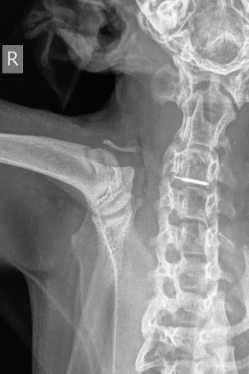

Röntgenonderzoek van de verwijzend dierenarts toont de chip er hoogte van het wervelkanaal op C3-C4.

Op röntgenopnamen van de cervicale hals is de chip te zien ter hoogte van C3-C4.